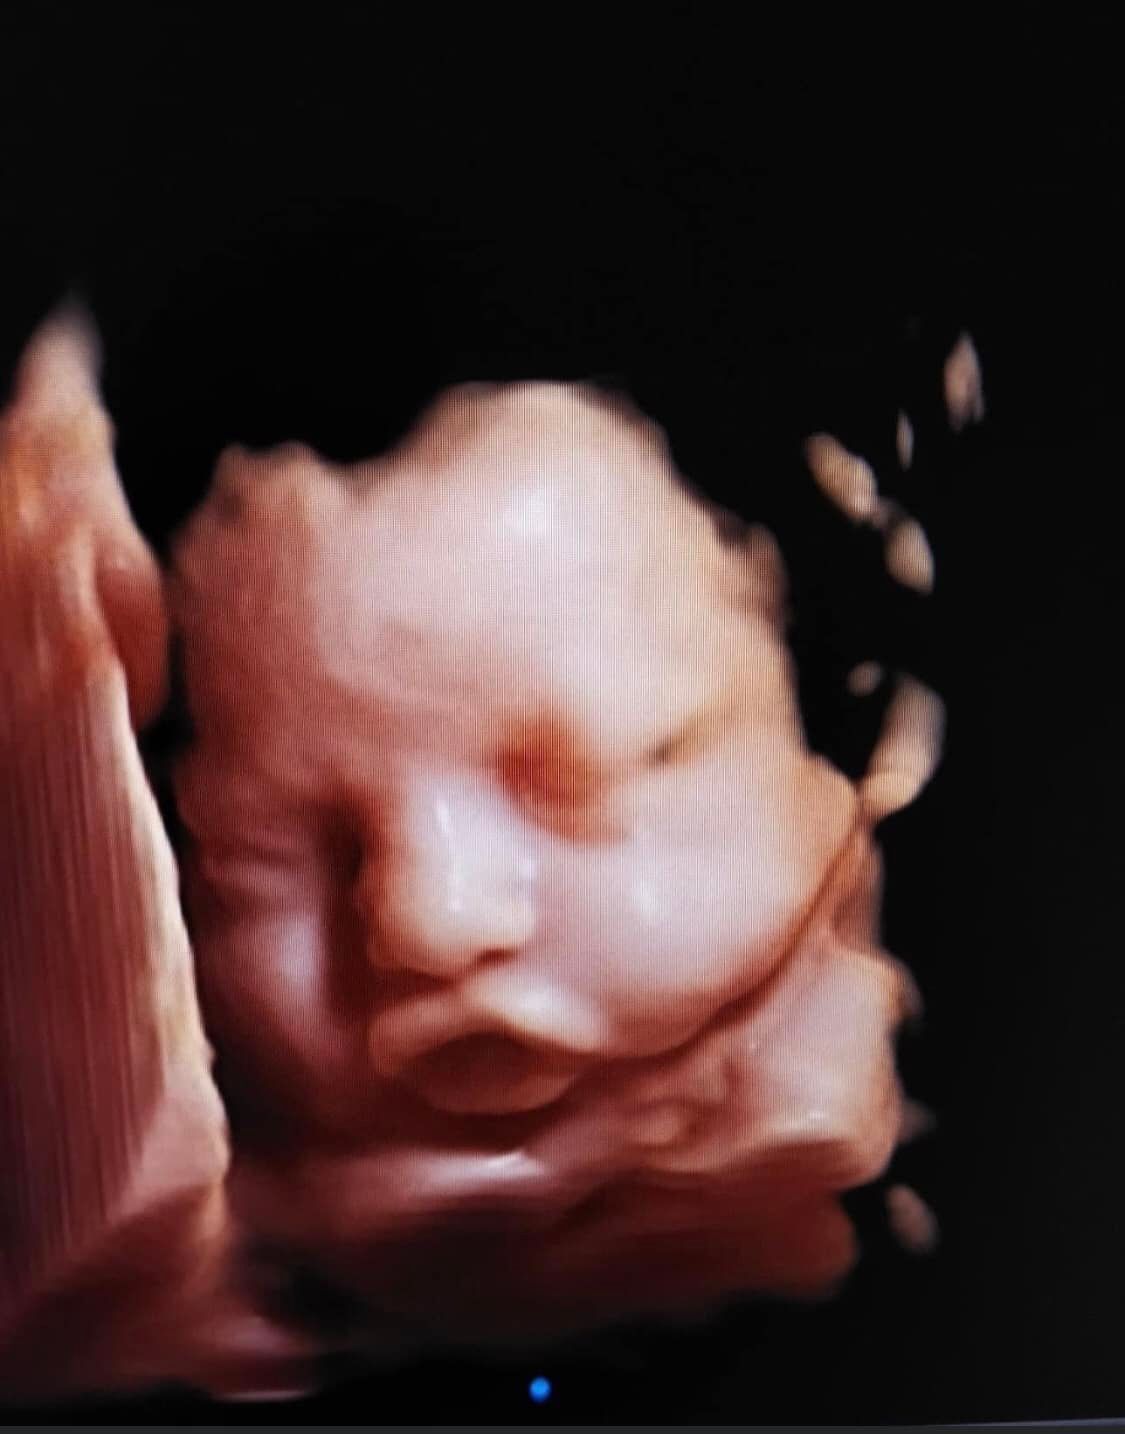

Obstetrics and gynecology: 3D ultrasound is commonly used in obstetrics to visualize the fetus and assess fetal growth and development. It can also be used to diagnose chromosomal abnormalities and congenital defects. In gynecology, it can be used to evaluate the uterus and ovaries, as well as to guide biopsy procedures.